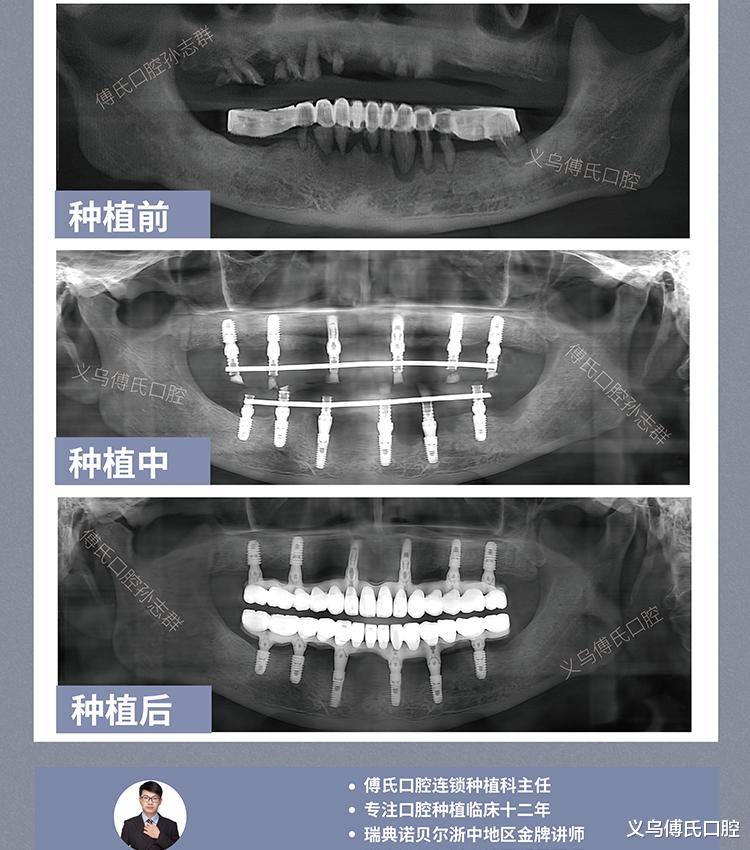

3、看案例:真实案例比宣传更重要。

①查看术前术后对比照、口内CT对比;②优先选择上千例种植案例的医生;③复杂案例越多,说明技术越全面。

种植案例分享